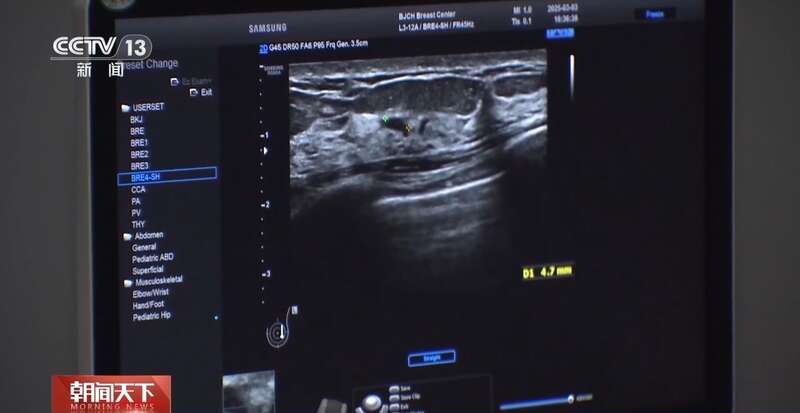

钼靶和超声,是目前我国乳腺癌筛查的主要检查方法。两项检查,各有优劣,40岁以下的女性,一般来说,更适合做超声检查。

北京大学肿瘤医院乳腺癌预防治疗中心副主任医师霍苓:(超声检查)首先是没有辐射,然后安全性好,所以不同年龄阶段的女性,年轻女性孕妇,还有需要频繁检查的女性都是可以经常做的。钼靶是一个X线检查,它是有辐射的,做的时候会把病人的乳房整个夹成一个片状,所以病人的耐受程度也会差一点。

虽然超声没有辐射,但对于微小钙化,钼靶检查的敏感性更高。

根据国际通行的BI-RADS分级标准,对结节予以0至6级分类。专家表示,3级以上的结节,女性需要重视,按时复查或尽快就诊。

北京大学肿瘤医院乳腺癌预防治疗中心副主任医师霍苓:3级,一般半年要进行重复的超声检查;4级相对来讲恶性风险跨度比较大,一般建议要穿刺活检;5级的话就是高度怀疑恶性,所以一定要穿刺明确诊断,进行后续的治疗;6级就是已经在其他地方穿刺确诊为乳腺癌的病灶。